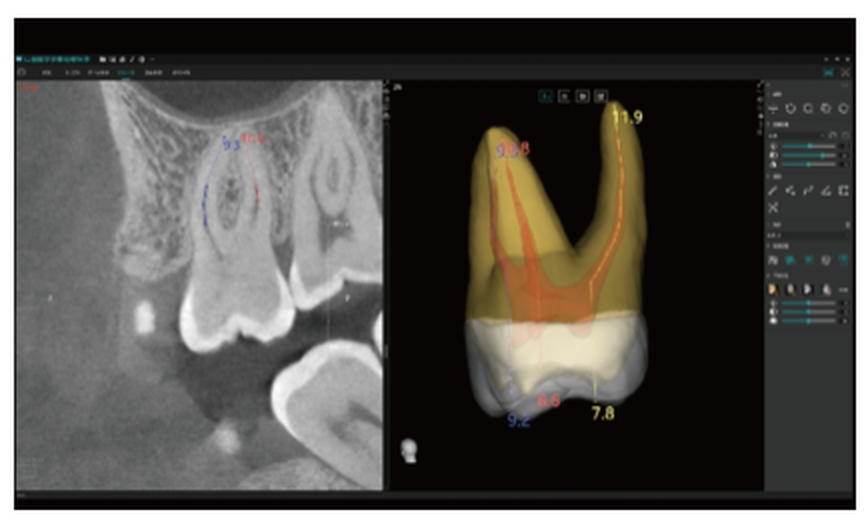

Medição Automática do Canal Radicular

Medição do Canal Radicular: precisa, automática e fiável — evita erros manuais e permite o planeamento pré-operatório.

Planeamento Endodôntico Inteligente: mede com precisão o comprimento do canal radicular, garantindo um tratamento previsível e eficiente.

Simulação de Acesso ao Canal Radicular

Apresenta dinamicamente as posições dos orifícios dos canais radiculares, auxiliando a educação do paciente.

Apoia os clínicos no planeamento do tratamento e na definição da estratégia terapêutica.